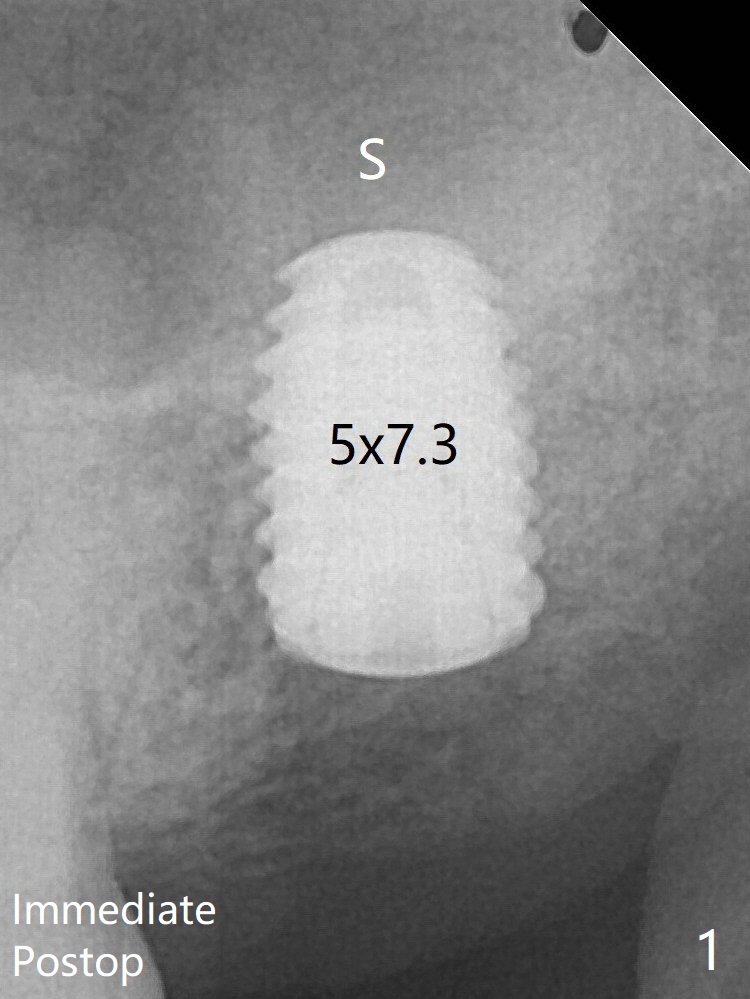

With sensor I, there is less distortion and angulation (Fig.4, as compared to Fig.1 (sensor II)).   A 5.5 mm profile drill is used prior to healing abutment placement.